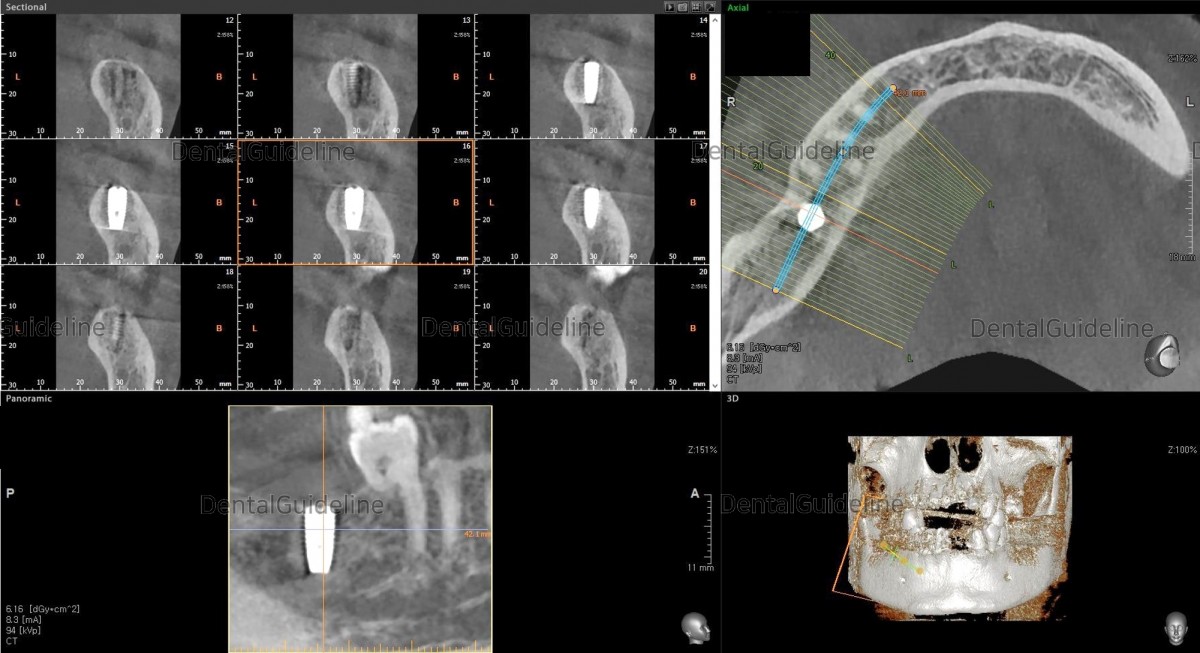

- Simple simulation on the CBCT image.

-Post-op CBCT.

- implant surgery was simply simulated on the CBCT scanned image.

- post-op CBCT.